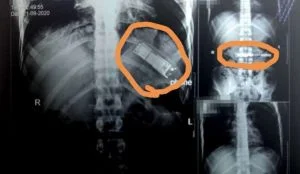

كشفت فحوص بالأشعة أجريت لمريض بمستشفيات بنها الجامعية في مصر، عن وجود هاتف محمول في معدته بقي هناك بعد أن قام بابتلاعه

منذ 7 أشهر.

إنه تم استقبال المريض ، من مدينة كفر شكر بالقليوبية، وتم إجراء أشعة تليفزيونية على الصدر والبطن، حيث تم اكتشاف

وجود هاتف محمول بمعدته.